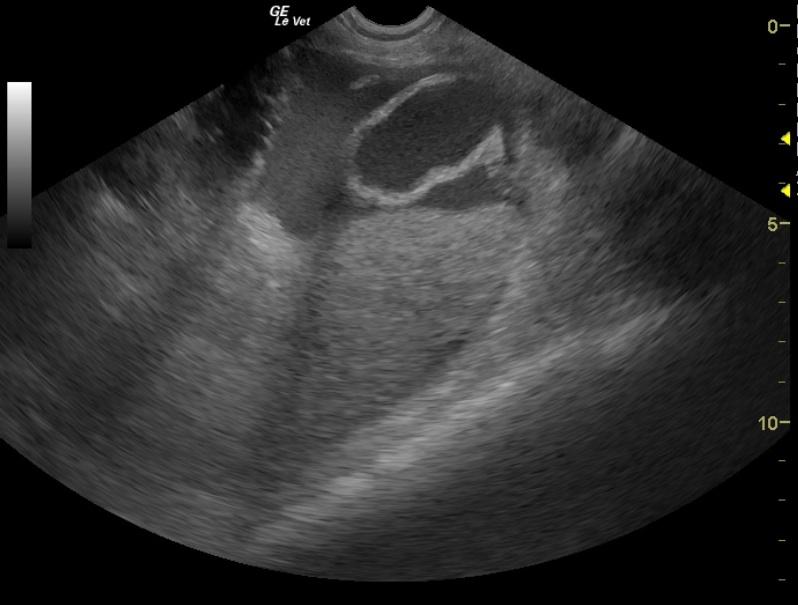

The abdomen in this patient presented a moderate amount of mildly echogenic free fluid, which was found to be hemorrhagic modified transudate on abdominocentesis. The uterus was dilated and irregular. This is consistent with pyometra with some omental reactivity. Rupture could not be ruled out given the hemorrhagic modified transudate free fluid.

Pyometra. Undefined hemorrhagic free fluid in the abdomen.

Pyometra. Undefined hemorrhagic free fluid in the abdomen. Potential underlying immune mediated disease or neoplasia given the anemia.